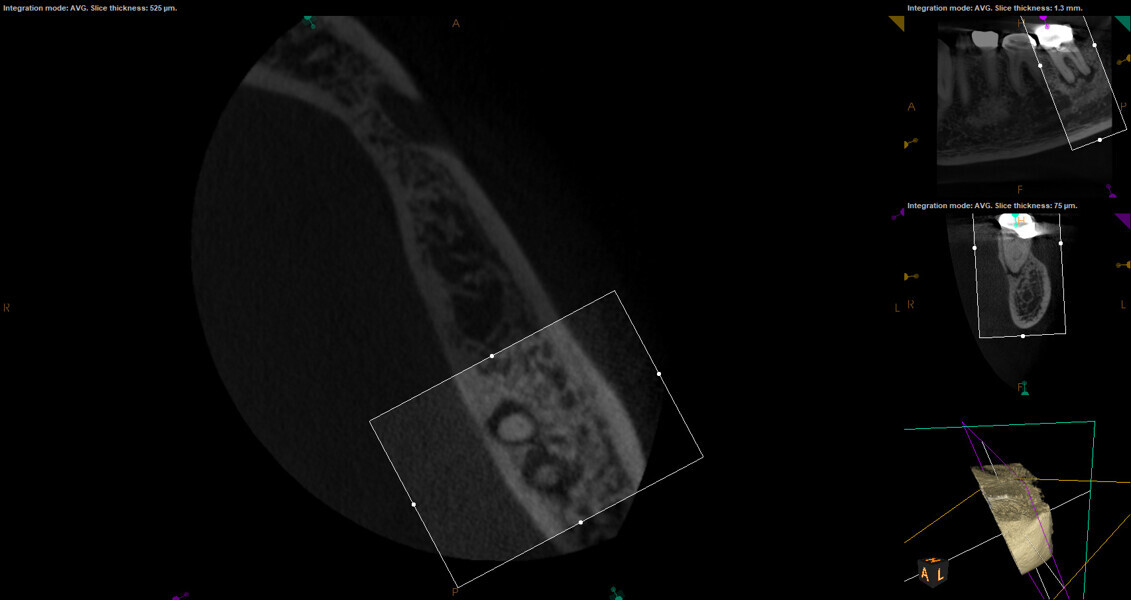

Fig. 17a: Case assisted with CBCT to determine anatomy pre-operatively. Note the multiple cross sections moving apically and the correlation to the 2-D view. Note also the conservative taper in relation to the root width. (Courtesy of Dr. Brett Gilbert)

Fig. 17b: Case assisted with CBCT to determine anatomy pre-operatively. Note the multiple cross sections moving apically and the correlation to the 2-D view. Note also the conservative taper in relation to the root width. (Courtesy of Dr. Brett Gilbert)

Fig. 17c: Case assisted with CBCT to determine anatomy pre-operatively. Note the multiple cross sections moving apically and the correlation to the 2-D view. Note also the conservative taper in relation to the root width. (Courtesy of Dr. Brett Gilbert)

Fig. 17d: Case assisted with CBCT to determine anatomy pre-operatively. Note the multiple cross sections moving apically and the correlation to the 2-D view. Note also the conservative taper in relation to the root width. (Courtesy of Dr. Brett Gilbert)

Fig. 17e: Case assisted with CBCT to determine anatomy pre-operatively. Note the multiple cross sections moving apically and the correlation to the 2-D view. Note also the conservative taper in relation to the root width. (Courtesy of Dr. Brett Gilbert)

Fig. 17f: Case assisted with CBCT to determine anatomy pre-operatively. Note the multiple cross sections moving apically and the correlation to the 2-D view. Note also the conservative taper in relation to the root width. (Courtesy of Dr. Brett Gilbert)